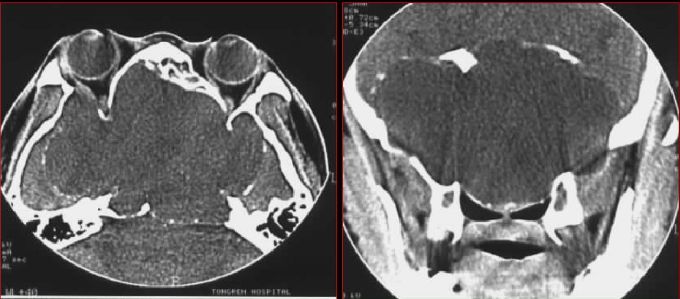

鼻窦炎—骨质改变

鼻窦炎—骨质增生

鼻窦炎—骨质增生及脑膜炎